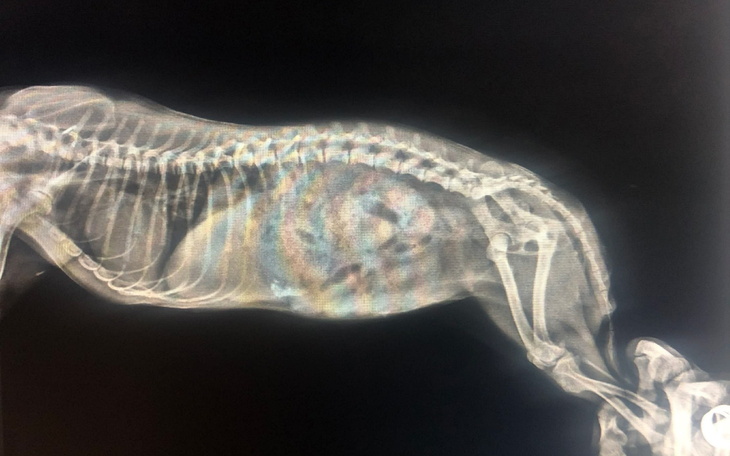

Pomimo ogromu starań, leczenia, konsultacji i dwóch przeprowadzonych RTG, stan jej tylnych łapek wciąż jest zagadką. Co więcej – zauważyliśmy, że dziewczynka nie trzyma kału, co może wskazywać na poważniejsze problemy neurologiczne...

To jedyny sposób, aby sprawdzić, co tak naprawdę dzieje się w jej kręgosłupie i czy istnieje jeszcze jakakolwiek szansa na poprawę jej stanu, komfortu i życia bez bólu.